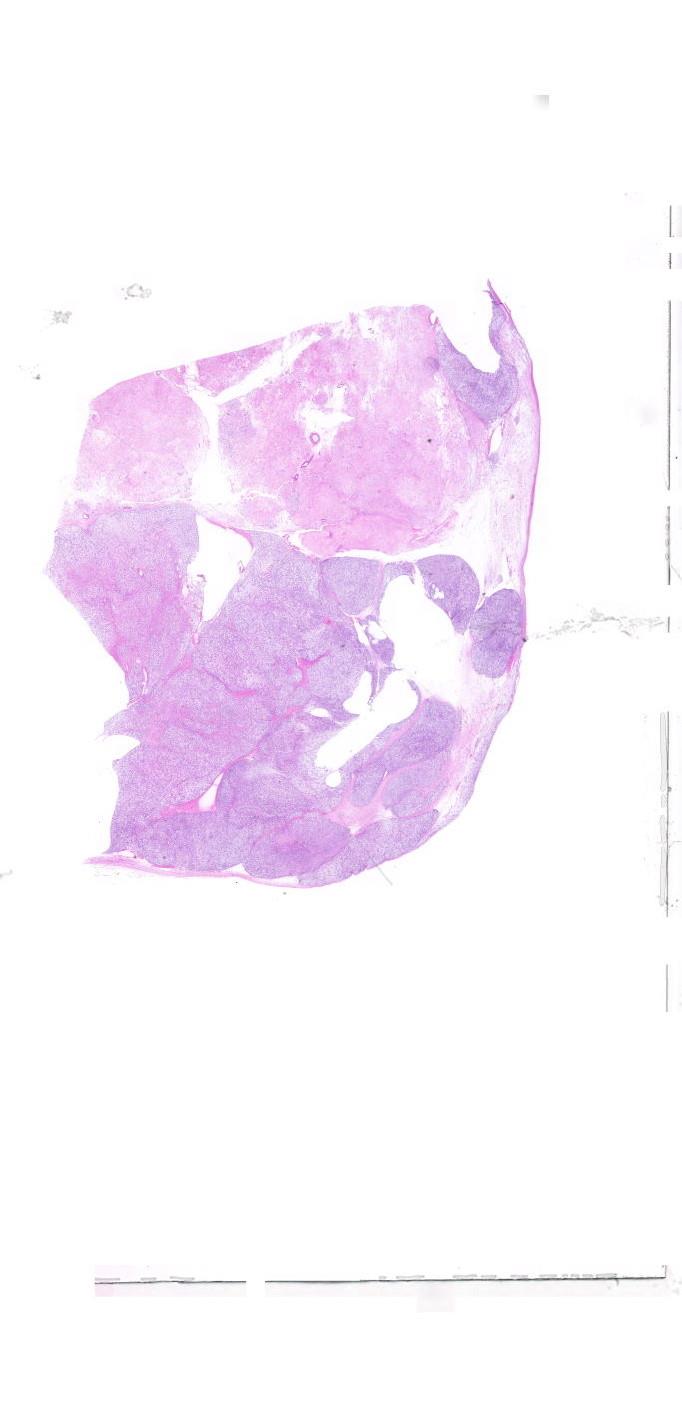

左卵巢 |

女, 69岁, 患者因“自行扪及腹部包块20+天”入院。彩超:盆腔内及下腹部... |

四川大学华西第二医院 |

待公布 |